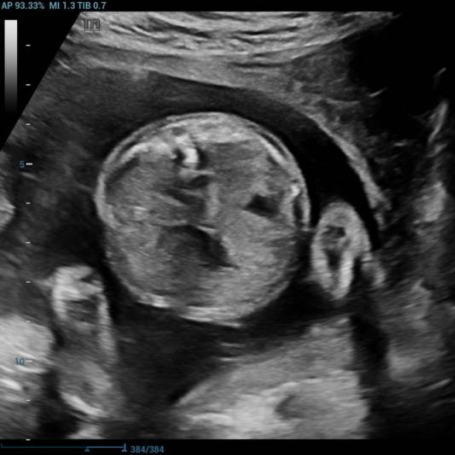

多年来,贵州航天医院各科室紧跟医学前沿,不断强技术、补短板,大力开展新技术、新项目,完成了许多高精尖、高难度、本地区“首例”的技术,填补了医院医疗技术空白,满足了群众日益增长的医疗需求。 复杂性双胎超声监护耗时耗力,技术难度大,风险高,为填补本地区复杂性双胎的超声监护技术空白,我院超声科在遵义市率先开展了此项技术,有效满足了双胎孕妇产检需求,保障了双胎新生儿的平安健康。 本期,我们将为大家带来超声科特色技术——复杂性双胎的超声监护。 案例分享 案例一 28岁的孕妇,自然受孕,怀有单绒毛膜双羊膜囊双胎(MCDA),在我院定期产检的过程中,孕32周超声检查发现两个胎儿的大脑中动脉血流流速(MCA-PSV)相差>0.7倍数的正常值(MoM),高度怀疑发生了双胎贫血红细胞增多序列征(TAPS)。为进一步明确诊断,产科立即组织超声科、手术室、新生儿科等科室进行多学科会诊(MDT),诊断为:双胎贫血红细胞增多序列征(TAPS),在征得孕妇及其家属的同意后,决定提前分娩,及时保障了两名胎儿的生命和健康。 双胎大脑中动脉血流 双胎贫血红细胞增多序列征(TAPS) 案例二 一名26岁的孕妇,是完全双角子宫,且为左侧子宫妊娠,怀有单绒毛膜双羊膜囊双胎(MCDA),一直在我院规律产检,孕16周时,超声检查发现双胎生长不一致,体重相差超过25%,考虑子宫畸形合并早发选择性胎儿宫内生长受限。孕妇在咨询相关上级医院专家后,得到减胎的建议,又前来我院咨询,在我院超声科和产科的合作下,查阅了大量文献、认真评估检查报告后,建议孕妇继续双胎妊娠。在规律、严密的超声监护下,双胎除体重差异外未出现严重胎儿并发症,在34周进行了分娩,截至目前,新生儿生长发育均正常。 胎儿生长曲线及子宫畸形三维重建 出生时体重差异 十月龄时 案例三 一名30岁的孕妇,自然受孕,怀有单绒毛膜双羊膜囊双胎(MCDA),在孕22周时超声检查发现双胎发生了选择性胎儿宫内生长受限,遂转诊到上级医院拟行胎儿镜治疗,但在行治疗的前一天,较小的胎儿在宫内发生死亡,在充分与孕妇及家属沟通后,要求继续妊娠,在定期规范的产检下,严密监测胎儿生长发育及胎儿颅脑MRI影像,最终在孕37周时通过剖宫产分娩,目前新生儿生长发育情况良好。 双胎之一胎死宫内(右图) 贵州航天医院自2021年开展复杂性双胎的超声监护以来,已服务大量双胎孕妇,集齐了所有单绒毛膜双羊膜囊双胎(MCDA)并发症病例,由经验丰富的超声医师进行此项检查,产科专业团队进行双胎的规范化监护和分娩,并与重庆医科大学附属第一医院建立了转诊通道,能够及时获得该院专家的指导和支持,为广大孕产妇提供优质、全面的医疗保障。 点击跳转贵州航天医院便民服务电话 什么是复杂性双胎的超声监护 “双胎”被称为产科之王,单绒毛膜双胎则为王中王,主要是因为单绒毛膜双羊膜囊双胎(MCDA)两胎儿共用一个胎盘,胎盘中存在血管吻合。 双胎妊娠的产前筛查及诊断主要依靠超声,相对于单胎妊娠,双胎妊娠并不是单胎检查的重复,双胎妊娠尤其是复杂性双胎的超声诊断更为重要的是关注双胎间循环的关联,双胎间生理及病理改变的相互影响,双胎间血流动力学监测及双胎间差异比较。 超声如何诊断 复杂性双胎并发症 在孕14周以前,超声要明确双胎的绒毛膜性:是单绒毛膜(MC)还是双绒毛膜(DC);孕10周前,可以通过孕囊的个数确定绒毛膜性;孕11周—14周,可以通过胎儿的性别、双胎之间隔膜的厚度、双胎儿分隔膜处胎盘的形态等来区分绒毛膜性。 双绒毛膜双胎的管理和单胎差不多,基本不需要增加超声检查的频次。单绒毛膜的管理相对谨慎,按照国际国内指南规范,单绒毛膜双胎自第16周起,每两周对双胎儿进行生长发育评估及血流检查。 复杂性双胎的超声监护,对超声医生技术要求较高,孕早期需对双胎的绒毛膜性进行精确判断;产科医生根据绒毛膜性制定孕期的产检计划;超声医生掌握胎儿宫内情况,及时与产科医生沟通,精确了解胎儿宫内安危后制定合适的治疗方案,给出适当的终止妊娠时机;复杂性双胎一般都面临早产的风险,所以新生儿团队的专业保障不可或缺,降低新生儿出生后的并发症及提高新生儿生活质量。复杂性双胎的较好妊娠结局,是通过孕期超声科、产科紧密合作,及新生儿出生后新生儿科管理多学科团队合作所获得的。 贵州航天医院超声科专家团队 吴艳辉 超声科 学科带头人 主任医师 专业擅长:从事超声诊断工作约30年,对心血管、小器官超声、超声引导下介入等具有丰富的临床经验。 骆科美 超声科 副主任医师 专业擅长:从事超声诊断工作33年,对胎儿心脏及颅脑、妇产超声诊断、盆底超声等诊断具有丰富的临床经验。 胡大海 超声科 副主任医师 专业擅长:从事超声工作17年,对心血管、外周血管、浅表器官超声诊断等具有丰富的临床经验。 刘 敏 超声科 副主任医师 专业擅长:从事超声诊断工作20余年,对妇产科超声、心脏血管超声诊断具有丰富的临床经验。 贵州航天医院超声科简介 贵州航天医院超声科配备多种超声检查设备(飞利浦彩超(IU-22、IU-Elite、HD11、Q5、Q7),迈瑞超声I9、DC-6、DC-8、GE-E8及床旁机,彩色超声诊断仪等),设有心血管诊室、妇产科诊室、腹部诊室、绿色通道、浅表小器官等检查室。 • ✦ 专科特色 ✦ • 四肢血管超声检查、双胎产前筛查及超声监护、超声造影检查技术、介入超声临床应用、经颅脑实质超声辅助筛查诊断帕金森病、女性性早熟超声诊断、盆底超声检查等。 NT超声检查 超声介入引导 肝脏超声造影 甲状腺造影 颅脑超声帕金森辅助检查 乳腺超声造影 上肢动静脉造瘘超声检查 双胎超声筛查 下肢血管超声检查 右心造影 • ✦ 诊疗范围 ✦ • 科室业务覆盖腹部、泌尿、妇科、产科(常规、NT筛查、III级筛查超声检查及高危妊娠监护)、成人心脏、外周血管、浅表器官(包含甲状腺、乳腺、阴囊、眼睛等)、颅脑(小儿颅脑、成人颅脑)、小儿肺超、造影、盆底、腹直肌、肌骨神经等检查及各种介入引导。